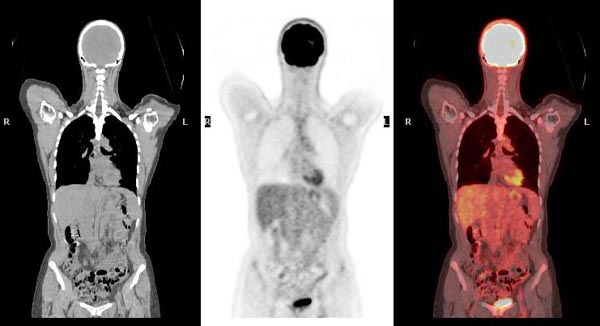

Positron Emission Tomography (PET)

Positron emission tomography (PET) also serves as another imaging modality that can help detect the presence of SCLC tumour cells or any possible spread to other parts of the body of the patient (Treadwell et al., 2016).

What can PET bring to SCLC patients?

An advantage of using PET with the 18F-FDG radiotracer is the ability to distinguish tumours such as SCLC from nodules or masses, which are often mistaken for tumours or other pathologies and cannot be detected with other imaging modalities.

- However, a disadvantage of PET is that the resulting images would not be able to show the necessary anatomical details that would help the doctor diagnose a patient.

How can PET be combined with other imaging modalities?

- Usually, a PET scan can be combined with other imaging modalities and performed at the same time, such as CT, creating what is called a PET-CT scan (Treadwell et al., 2016).

- A PET-CT scan would compensate with the necessary anatomical details that would not be demonstrated if PET alone were used.

Why is SCLC often found after it has spread and what role PET scans play to help spot any pathologies?

- Research has shown that SCLC is a very aggressive type of cancer, which means it tends to spread to other parts of the body quite quickly, even in early stages (Decoster et al., 2008).

- By the time SCLC is diagnosed, in about 7 out of 10 people, the cancer has already spread to multiple sites, making it harder to treat.

- Due to the metastatic nature of SCLC as a cancer, SCLC patients may have an elevated 18F-FDG activity on PET scans in a certain area.

- This means that those areas are using a lot of glucose (sugar). This is called being “FDG-avid.”

- This is not something to worry about as being FDG-avid is only a term to indicate that cancer is present, but sometimes it could just be inflammation, an infection, or other pathologies within the patient (Hofman & Hicks, 2016).

- For example, in the same study by Hofman & Hicks (2016), an early-stage (T1N0) patient had an 18F-FDG lesion in their lower right abdomen.

- This simply means that the PET scan picked up a spot with increased activity, which might need further investigation, but is not necessarily alarming on its own.

- As a result, cancer cells will show up as bright spots on PET scan images.

Figure 2. PET scan procedure and considerations (Raymaakers, 2024).